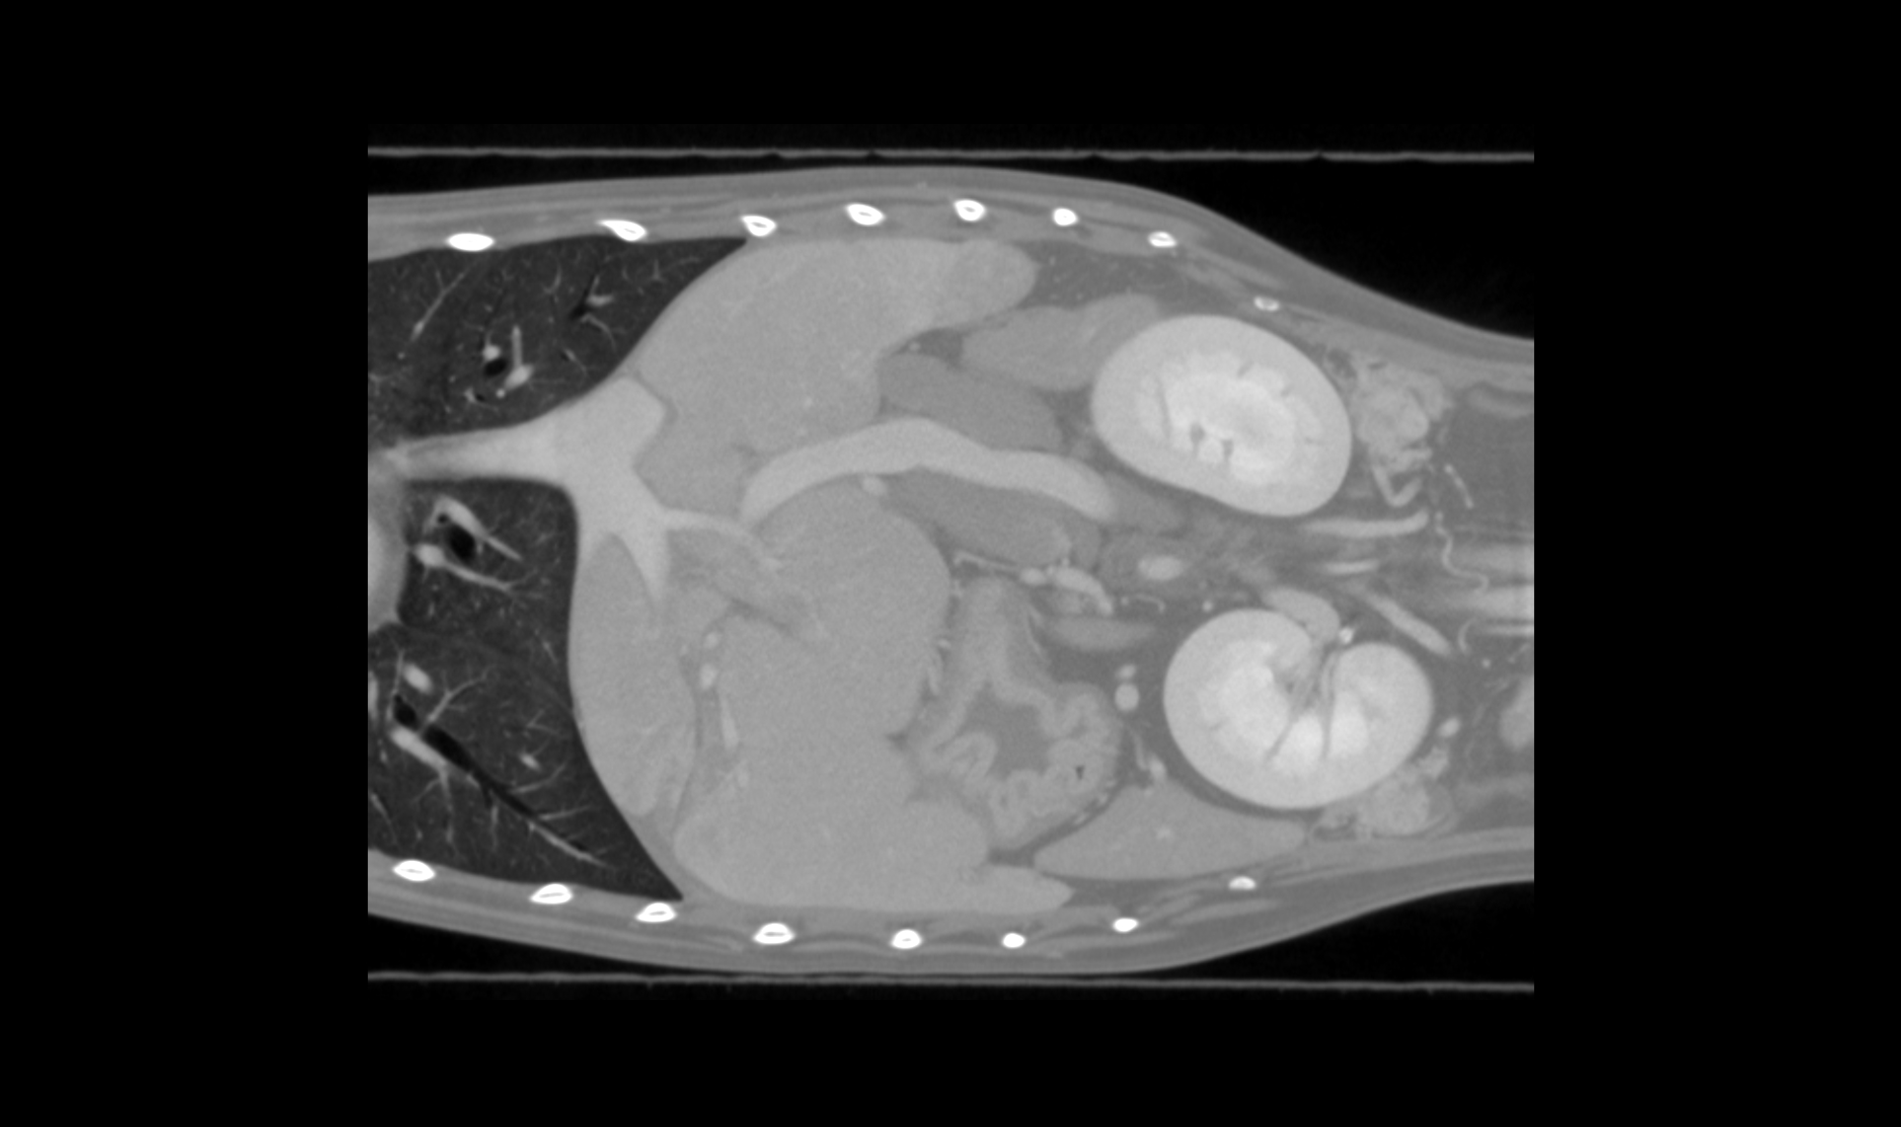

Dr Scott Echols

"We really don't know that much about the anatomy of a lot of these animals. However, we have never had a way to visualize it like we can now and each scan that we perform is a whole new treasure trove of data. We can literally see each blood vessel in the body."

DVM, DABVP,

Parrish Creek Veterinary Hospital & Diagnostic Center

Advancing Veterinary Care

Our scanners represent a point of reference for the veterinary profession, allowing targeted interventions and effective treatments for four-legged friends.